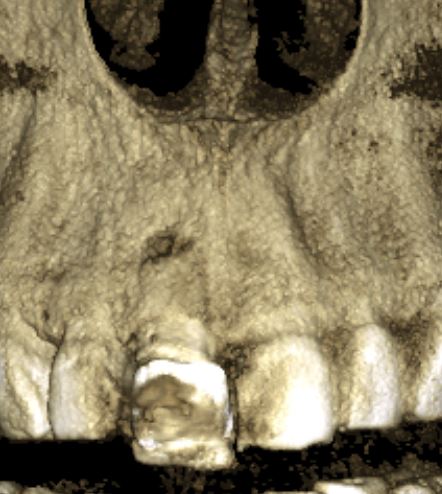

Наиболее важным исследованием для имплантологии и хирургии является компьютерная томография. Именно с помощью нее мы досконально изучаем костную ткань в области операции, определяем ее конфигурацию и структуру, планируем размер и положение импланта в челюстной кости:

Конечно, существуют доктора, которые игнорируют важность компьютерной томографии для имплантации, но нужно помнить, что в этом случае очень высока вероятность ошибки. А в такой сфере как хирургия, ошибки не очень желательны, верно?

Я работаю со всеми существующими программами дентальных томографов. Изучение снимка, его описание и все измерения всегда провожу самостоятельно. Идеальный вариант — изначальный снимок на диске, без распечаток, измерений и описаний.